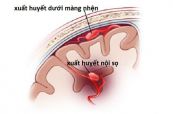

Xuất huyết dưới nhện là tình trạng máu bị rò rỉ chảy vào khoảng trống giữa não và màng bao quanh (màng não). Nếu như không được cấp cứu kịp thời, tình trạng này sẽ có thể gây ra các tổn thương nghiêm trọng tại não và thậm chí là tử vong. Tham khảo bài viết dưới đây để hiểu rõ hơn về hội chứng này nhé!

Xuất huyết dưới nhện là tình trạng máu bị rò rỉ chảy vào khoảng trống giữa não và màng bao quanh (màng não). Nếu như không được cấp cứu kịp thời, tình trạng này sẽ có thể gây ra các tổn thương nghiêm trọng tại não và thậm chí là tử vong. Vậy trên điện tâm đồ, bệnh lý này thể hiện như thế nào? Mời các bạn tham khảo bài viết dưới đây để hiểu rõ hơn nhé!